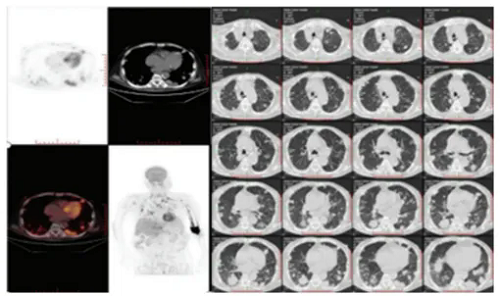

图1 从左图可以看到患者全身已出现大面积肿瘤转移

近期,在《Alternative Therapies in Health & Medicine》期刊中刊载的案例研究揭示了免疫疗法在晚期癌症治疗中的突破性进展,尤其是针对那些传统疗法效果有限的复杂病例。该研究报告详细记录了一位我国67岁男性肝癌患者的治疗过程。患者于2021年发现晚期肝癌,因伴随有大量肿瘤转移的情况,涉及肺部、淋巴结乃至骨髓,病情极度不乐观。